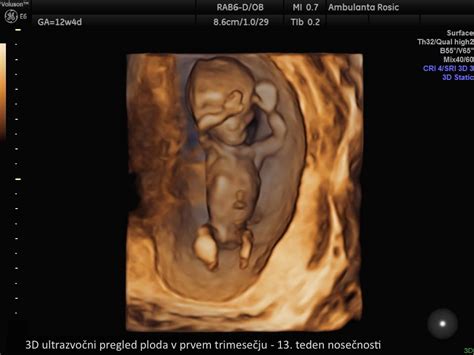

- 3D/4D ultrazvok ploda v prvem trimesečju: Ta napredna tehnika omogoča barvno in tridimenzionalno prikazovanje ploda, kar lahko staršem prinese edinstveno izkušnjo opazovanja svojega otroka že v zgodnji nosečnosti. Cena te storitve je običajno 25 € (za enojčke) in 35 € (za dvojčke), pogosto pa je vključena v ceno nuhalne svetline ali zgodnje morfologije.